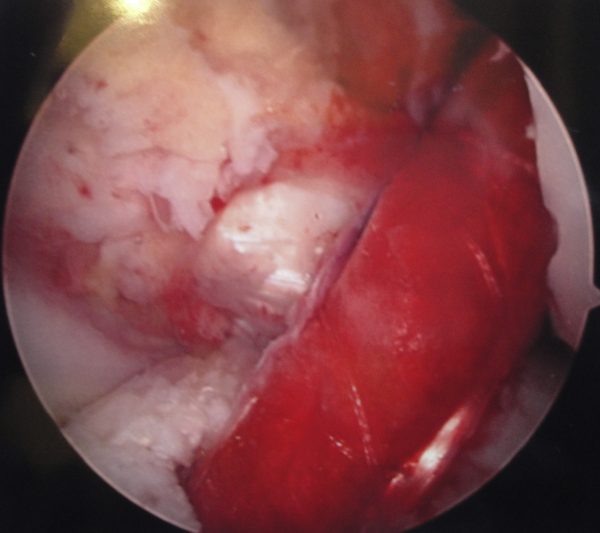

Institutional review board approval was obtained. Patients 21-years of age or younger who underwent ACLR utilizing autologous hamstrings and biologic augmentation (PRP and porous bovine collagen membrane, TenoMend™, Collagen Matrix, Ramsey, NJ), with a minimum of two years follow-up were enrolled. All patients completed physical therapy and answered outcome questionnaires, including IKDC, Lysholm, Tegner and SANE. They also answered questions concerning whether they had sustained an ipsilateral or contralateral ACL injury since their initial ACLR, positive family history for ACL injury, return to the same sport after ACLR that they had played previously and subsequent surgery on the reconstructed knee since the ACLR (Figure 1).